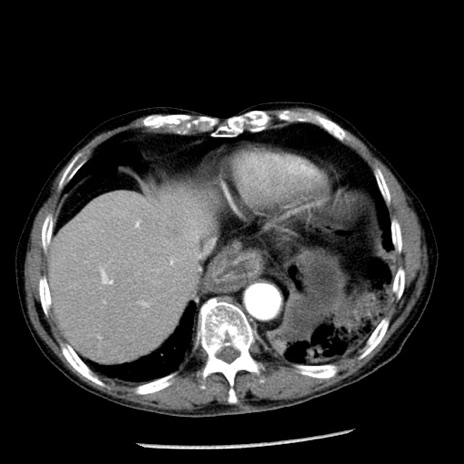

症例26(横断像)

【症例】80歳代男性

【主訴】嘔吐

【現病歴】昨晩2回嘔吐あり、今朝になっても嘔吐あり。来院。

【既往歴】胃潰瘍

【身体所見】意識清明、BT 37.6℃、BP 166/95mmHg、HR 100bpm、SpO2 97%、腹部:平坦・軟、腸蠕動音聴取良好、圧痛なし。

【データ】WBC 21900、CRP 1.46